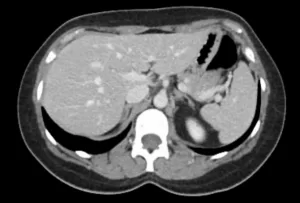

Fase nefrográfica

Derivação urinária em alça delgada na fossa ilíaca à esquerda. Houve boa distensão da alça de derivação, porém nota-se falha de enchimento de aspecto polipoide na fase excretora medindo cerca de 2,2 x 1,0 cm. Sugere-se prosseguir investigação.

• Mulher de 40 anos de idade com um Bricker ileal há mais de 25 anos por conta de um sarcoma pélvico

• Lesão polipoide na alça ileal da derivação urinária